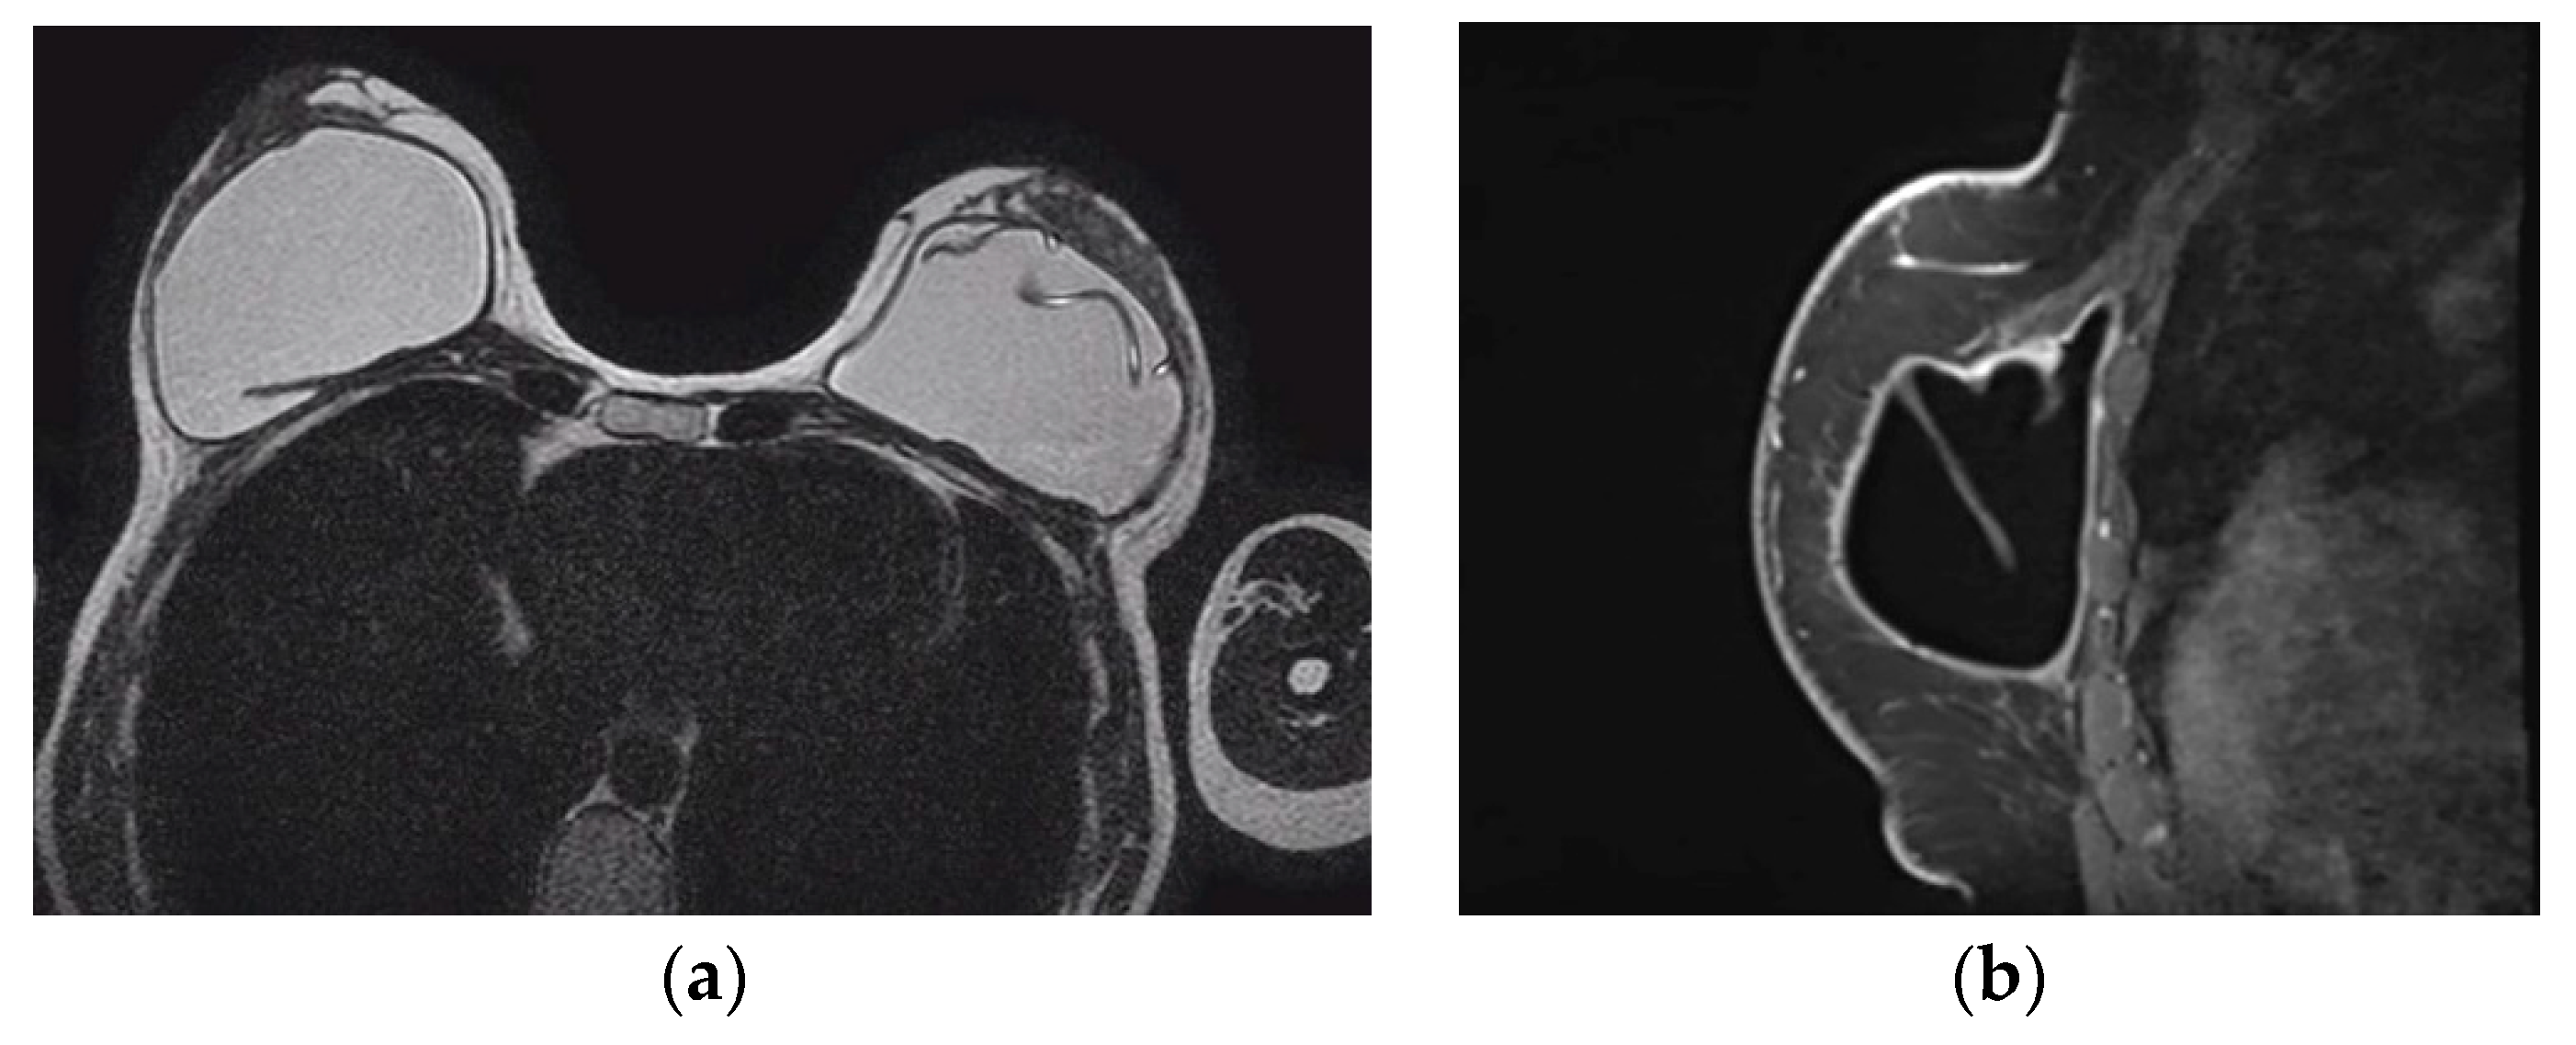

On mammography the reconstructed breast is consisted predominantly by fat and in case of muscle baring flaps muscle strands can be visible. Postoperative scarring and clips are common findings (Figure 1) [44].

The pedicled or free TRAM flap and the LD flap consist of the rectus abdominis and latissimus dorsi muscle respectively and also the overlying skin and subcutaneous fat. In the TRAM reconstruction the flap is recognized centrally along the anterior chest wall in axial images. In the LD reconstruction the flap is more eccentric with a tailed appearance of the muscle in the lateral breast as a result of the flipping and tunneling of the flap harvested from the back, differentiating it from a TRAM flap (Figure 2) [35]. In both cases the muscle atrophies over time. A thin low signal intensity curvilinear line parallel to the breast contour is often visible, best appreciated on sagittal images, representing the dermal layer of the lower abdominal or the dorsal wall [35,45]. The contact zone of the TRAM flap to the mastectomy site, that corresponds to the musculovascular pedicle may exhibit contrast enhancement [46].

The typical mammographic appearance of an implant is a radiopaque oval mass with smooth margins whose density varies depending on the filling material (Figure 3a). A band of soft density tissue surrounding the implant, with or without calcifications represents the thick fibrous capsule that is formulated after the implant insertion as a result of a foreign body reaction. Folds within the implant and the valve may be visible with the appropriate mammographic technique [47].

Ultrasonographically both saline and silicone implants are anechoic and the shell appears either as one echogenic line or as parallel echogenic lines. Internal folds may be recognized as wavy lines without disruption. The fibrous capsule is visible as an echogenic line parallel to the implant’s shell, sometimes with calcifications producing focal acoustic shadowing (Figure 3b). A small peri-implant fluid effusion is a normal finding. At implants with expanders the valve is visible and caution should be taken so that partially expanded implants should not be mistaken for ruptured implants [47].

Figure 1. Deep Inferior Epigastric Perforator (DIEP) reconstruction. (a) Mediolateral Oblique mammographic (MLO) view of the reconstructed breast depicts essentially fatty tissue and surgical clips (arrows); (b) Axial thoracic CT scan confirms the presence of a viable DIEP reconstruction with no complications.